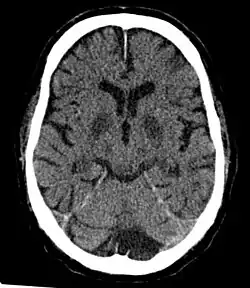

Bei einem Exit-Bag handelt es sich in der Regel um einen luftdichten Plastikbeutel, den der Sterbewillige sich selbst über den Kopf zieht oder gestülpt bekommt.[1] Dadurch wird die Person von der Umgebungsluft abgeschnitten und stattdessen einer ausreichend großen Füllmenge Inertgas, wie Stickstoff oder einem Edelgas, ausgesetzt.[2] Sauerstoffmangel führt innerhalb von 15 bis 20 Sekunden zur Bewusstlosigkeit. Hirnschäden entstehen nach ein bis zwei Minuten. Der Tod durch Atemstillstand tritt nach zwei bis 40 Minuten ein.[2][3]

Es sind signifikante Variabilität in Sterbedauer, und Verletzungsmustern durch Exit-Bags dokumentiert. Der Tod tritt in einer Zeitspanne zwischen zwei und 40 Minuten ein.[2] Lungenschäden können zur Zyanose und einem Ausfluss von Blut aus den Nasenöffnungen und aus der Mundhöhle führen.[7] Überlebende, die einer Hypoxie ausgesetzt werden, können dauerhafte Hirnschäden erleiden.[8]